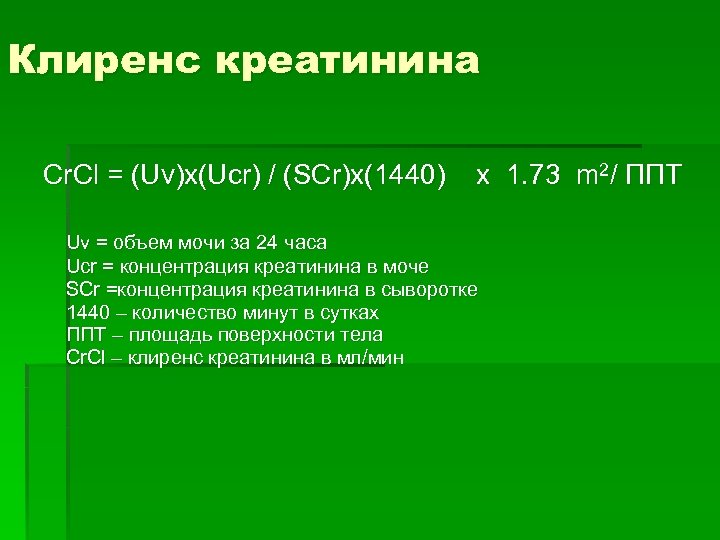

Клиренс креатинина Cr. Cl = (Uv)х(Ucr) / (SCr)х(1440) x 1. 73 m 2/ ППТ Uv = объем мочи за 24 часа Ucr = концентрация креатинина в моче SCr =концентрация креатинина в сыворотке 1440 – количество минут в сутках ППТ – площадь поверхности тела Cr. Cl – клиренс креатинина в мл/мин